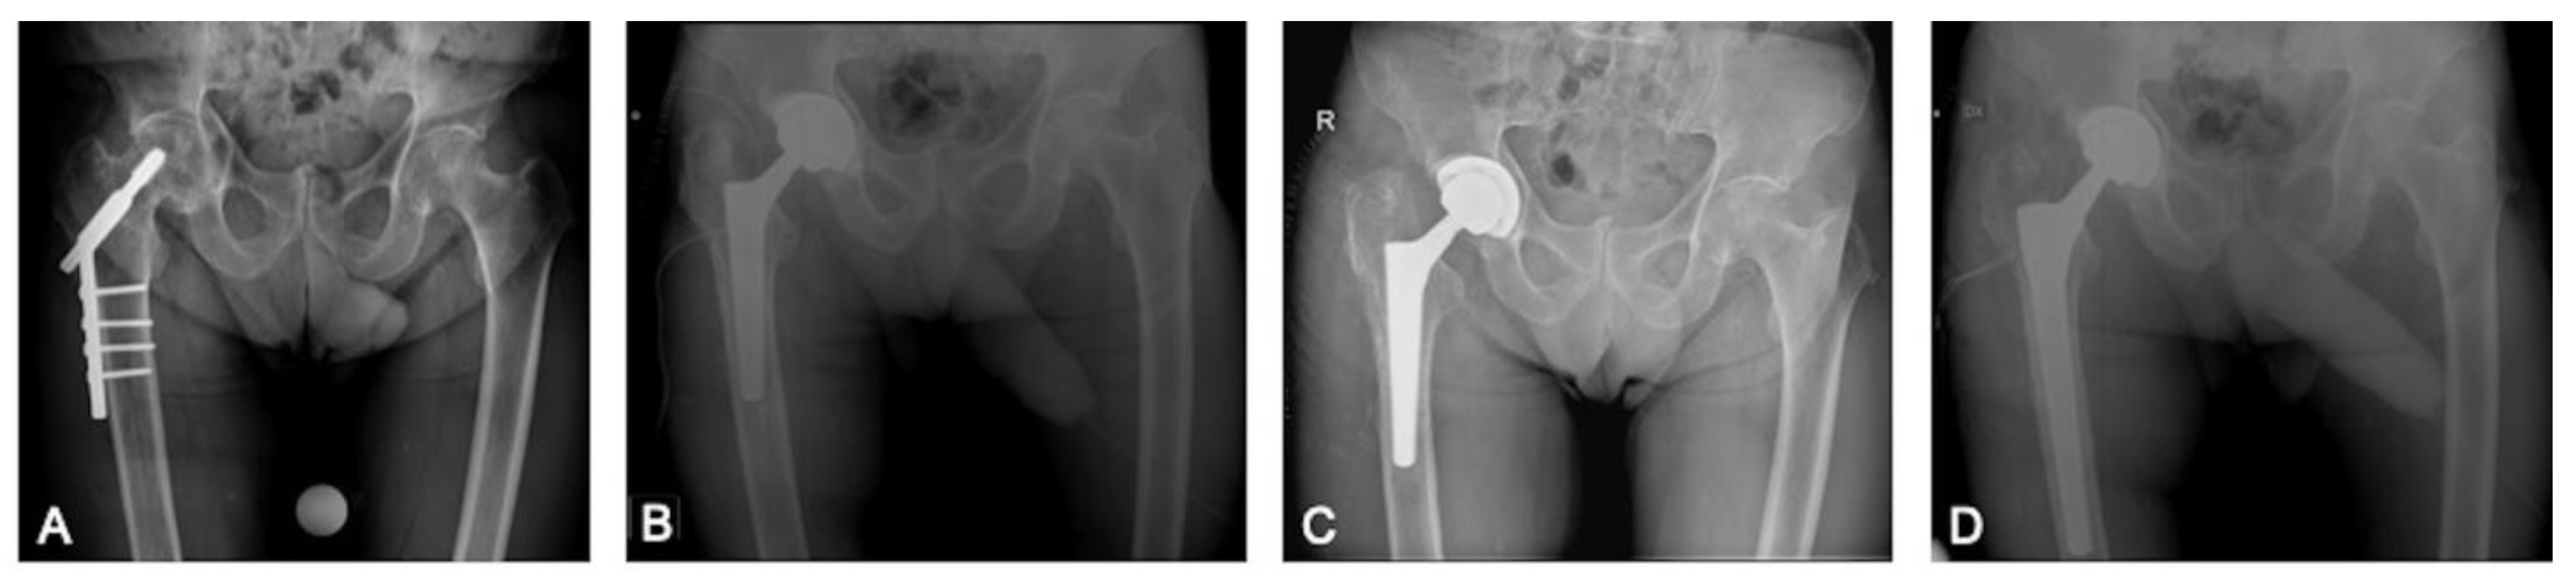

| Post-Traumatic Group | Post-Preventive Group | |

| Number of hips | 87 | 40 |

| Index surgery | ||

| Subtrochanteric fracture | 34 (39%) | - |

| Pertrochanteric fracture | 45 (51%) | - |

| Shaft fracture | 7 (8%) | - |

| Acetabular fracture | 1 (1%) | - |

| Hardware removed | ||

| Intramedullary nail | 31 (24%) | - |

| Küntscher nail | 1 (1%) | - |

| Dynamic hip screw | 14 (11%) | - |

| Screws | 35 (27%) | 13 (10%) |

| plate and screws | 6 (5%) | 9 (7%) |

| Type of femoral stem used for conversion THA | ||

| Cementless | ||

| Conventional tapered | 31 (24%) | 7 (6%) |

| Short tapered | 16 (13%) | 8 (6%) |

| Conical | 4 (3%) | 21 (17%) |

| Long revision | 31 (24%) | 4 (3%) |

| Resurfacing | 1 (1%) | - |

| Cemented | ||

| Conventional tapered | 4 (3%) | - |